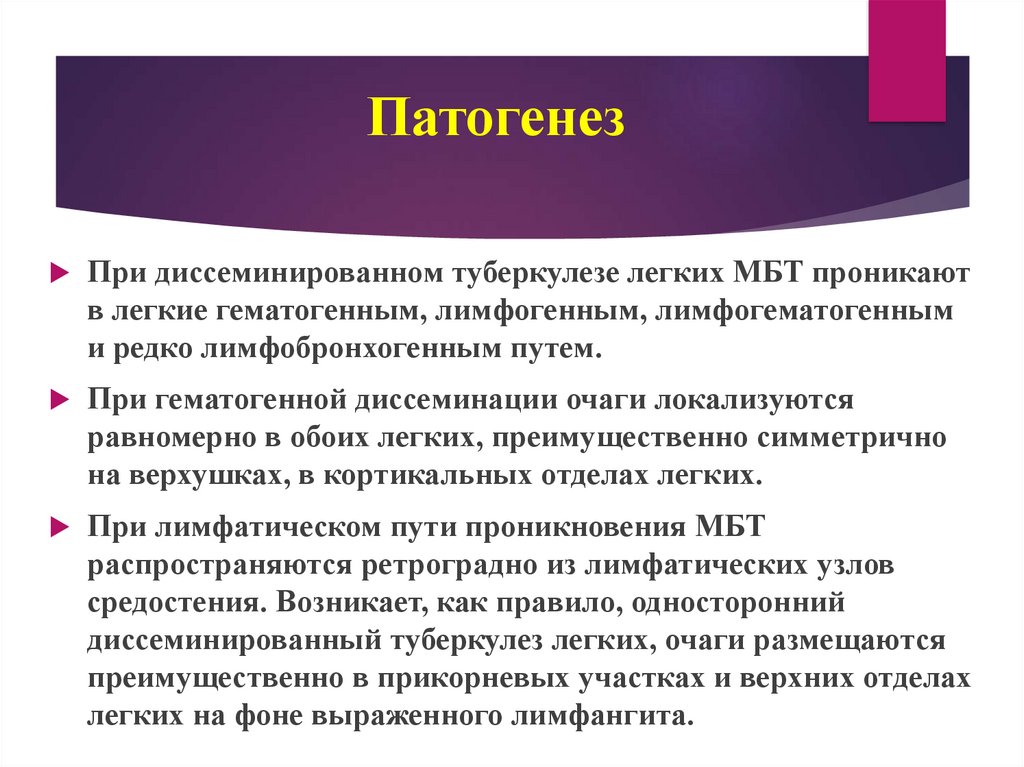

В клинической картине острого гематогенно диссеминированного туберкулеза преобладает